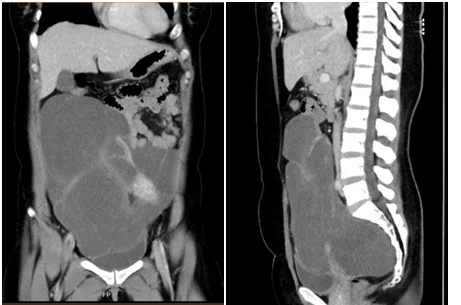

Hình CT scan khối u chiếm gần toàn bộ ổ bụng, từ vùng chậu lên đến sát gan

Qua thăm khám kết hợp với siêu âm, chụp CT, bác sĩ phát hiện chị A. có khối u rất lớn, chiếm 2/3 ổ bụng, chèn ép ruột, bọng đái. Ngày 4-7, chị A. được phẫu thuật, mặc dù khối u rất lớn dính vào ruột non, ruột già, bọng đái, tử cung, buồng trứng, vách chậu và xương cùng nhưng các bác sĩ vẫn cắt hoàn toàn khối u, bảo vệ an toàn các cơ quan khác, nhất là khi khối u len vào giữa xương cùng và trực tràng.

Khối bướu có kích thước 20x30 cm, cân nặng 2,8 kg, mô bướu rất bở, len lỏi vào các cơ quan khác nên việc mổ cắt trọn u là việc rất phức tạp.